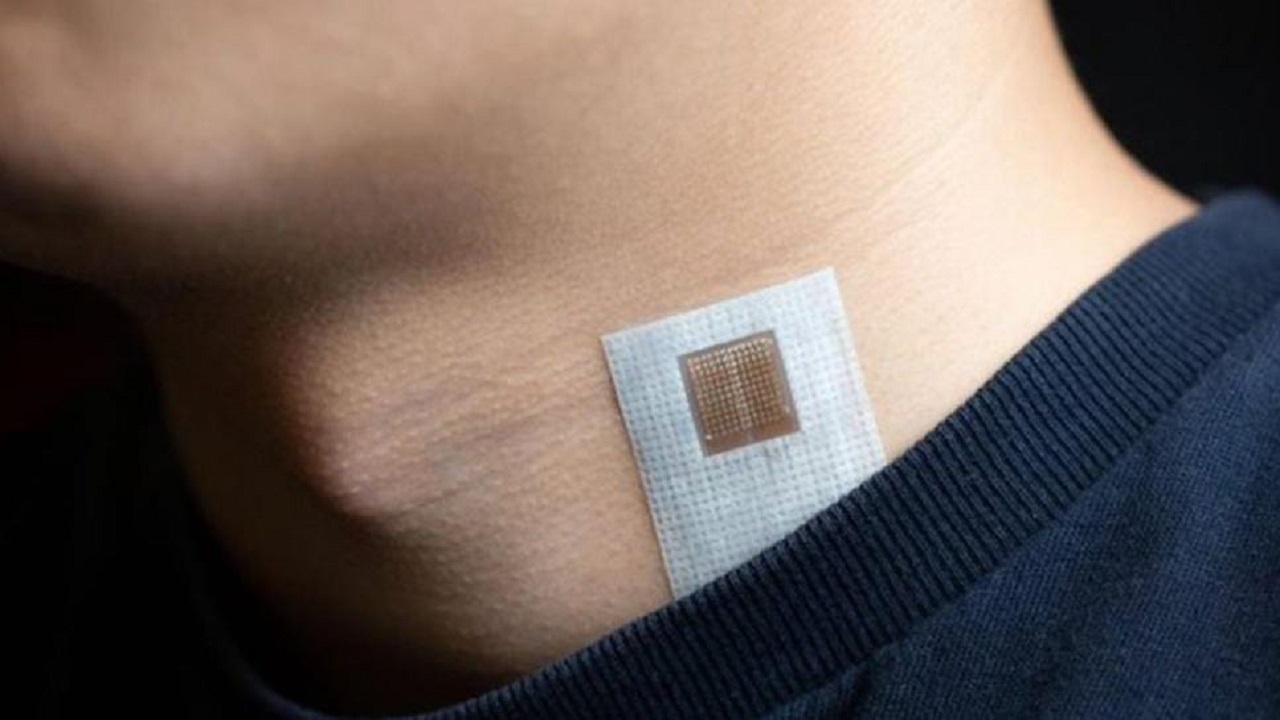

ابتكار لاصقة تنذر بالسكتة الدماغية والنوبة القلبية مبكراً

منذ 5 سنة

2

3292